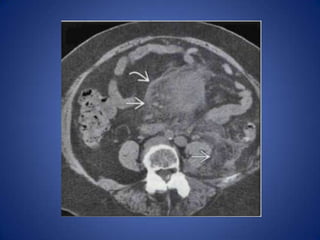

Sclerosing Mesenteritis

• Being diagnosed much more commonly as

cause of recurrent abdominal pain, usually

poorly localized

• "Misty mesentery" with cluster of jejunal

mesentery nodes with surrounding thin

capsule

• Often with history of prior similar episodes

• May respond to steroid therapy or resolve on

its own

Sclerosing Mesenteritis • Beingdiagnosed much more commonly as cause of recurrent abdominal pain, usually poorly localized • "Misty mesentery" with cluster of jejunal mesentery nodes with surrounding thin capsule • Often with history of prior similar episodes • May respond to steroid therapy or resolve on its own